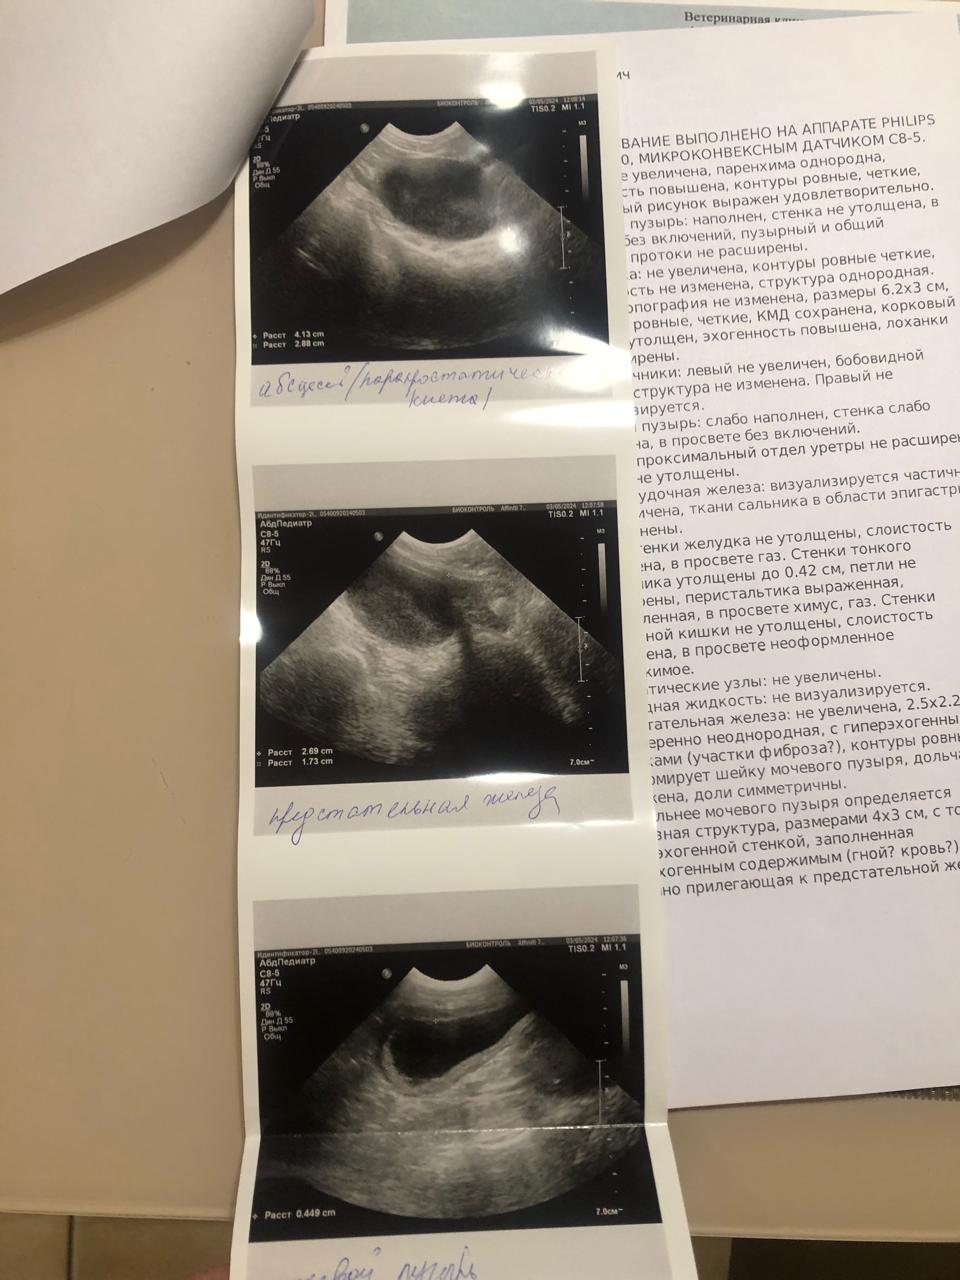

Визит в Био контроль.

Вложения

IMG-20240503-WA0115.jpg

IMG-20240503-WA0113.jpg

IMG-20240503-WA0111.jpg

IMG-20240503-WA0112.jpg

IMG-20240503-WA0110.jpg

Далее

IMG-20240503-WA0116.jpg

IMG-20240503-WA0114.jpg